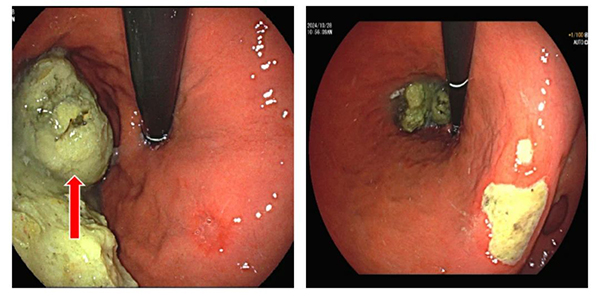

圖 2 胃鏡下見胃結(jié)石      圖 3 胃鏡下見胃角潰瘍